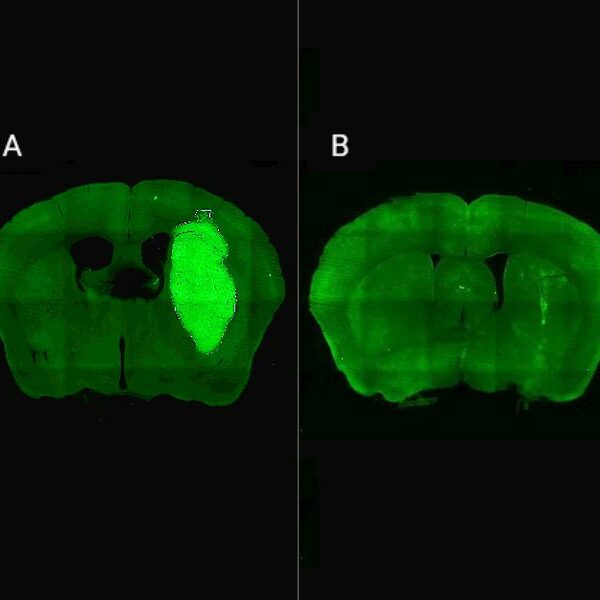

Un estudio liderado por científicos del CONICET mostró en animales que esa estrategia fortalece los circuitos del hipocampo, región clave para la generación de memorias nuevas y que resulta afectada en la enfermedad de Alzheimer. El trabajo logró explicar los mecanismos por los cuales ese abordaje podría restaurar funciones cognitivas. En los últimos años, la…